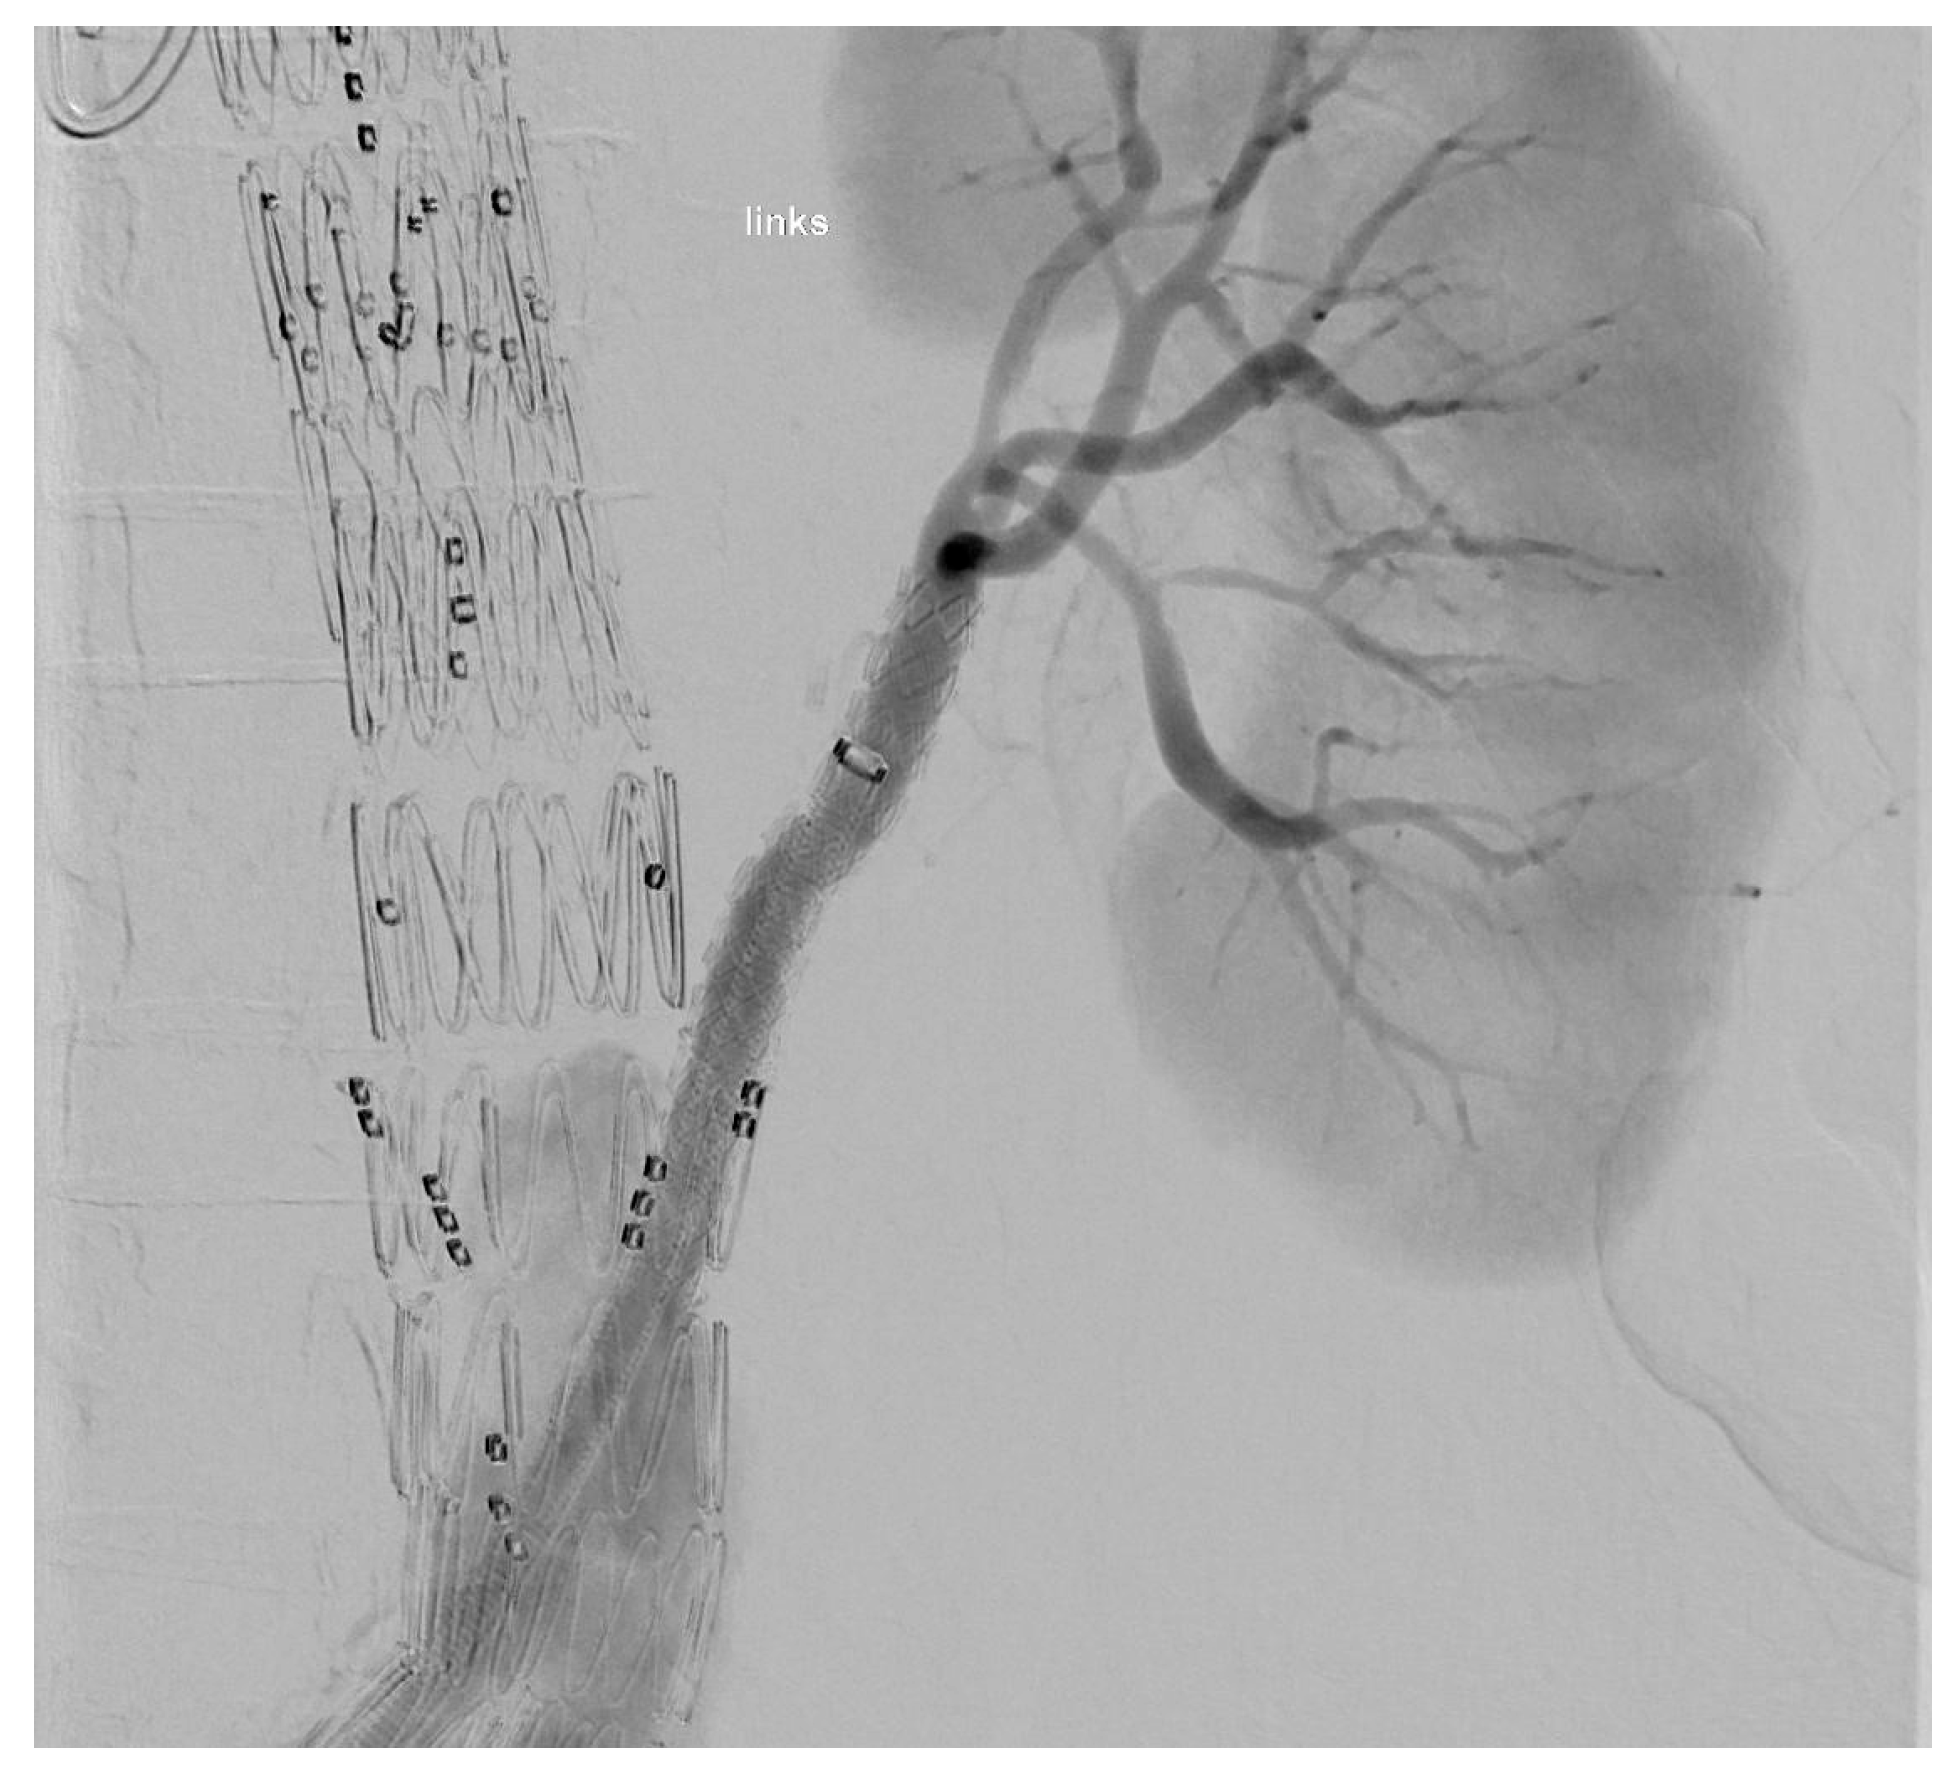

The target vessel of the upward-facing branch was always at least one of the renal arteries (Figure 2). In two cases, both renal arteries were connected through upward-facing branches, and in one case, we used it for an accessory renal artery.

Figure 2. XA during the procedure.